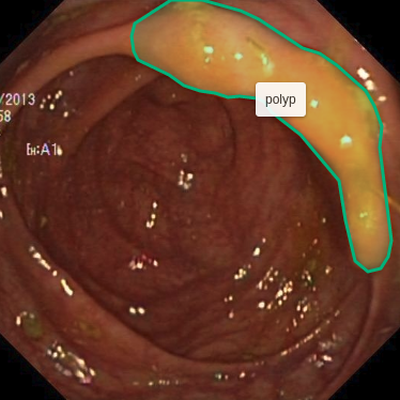

The goal of image segmentation is to assign a label to each pixel of the image so the pixels with the same label share specific characteristics, e.g., the pixels covered by the outline in the Figure 1 show a polyp. Manual segmentation by physicians is still the gold standard for most of the medical imaging modalities, for example, Magnetic Resonance Imaging for evaluating hippocampal atrophy in Alzheimer’s Disease [5] and tumor segmentation of glioma [27]. However, manual image segmentation is tedious, time-consuming, and subject to physician’s bias and inter-observer variation. Therefore, there is a need for an automated and efficient image segmentation technique.

Figure 1 shows example frames from the kvasir dataset where we have additionally marked the polyp tissue with green outline. After annotation, we exported the files to generate masks for each annotation. The exported JSON file contained all the information about the image and the coordinate points for generating the mask. To create a mask, we used ROI coordinates to draw contours on an empty black image and fill the contours with white color. The generated masks are a 1-bit color depth images with white foreground and black background. Figure 2 shows example images, their corresponding segmentation masks and bounding boxes from the Kvasir-SEG dataset.